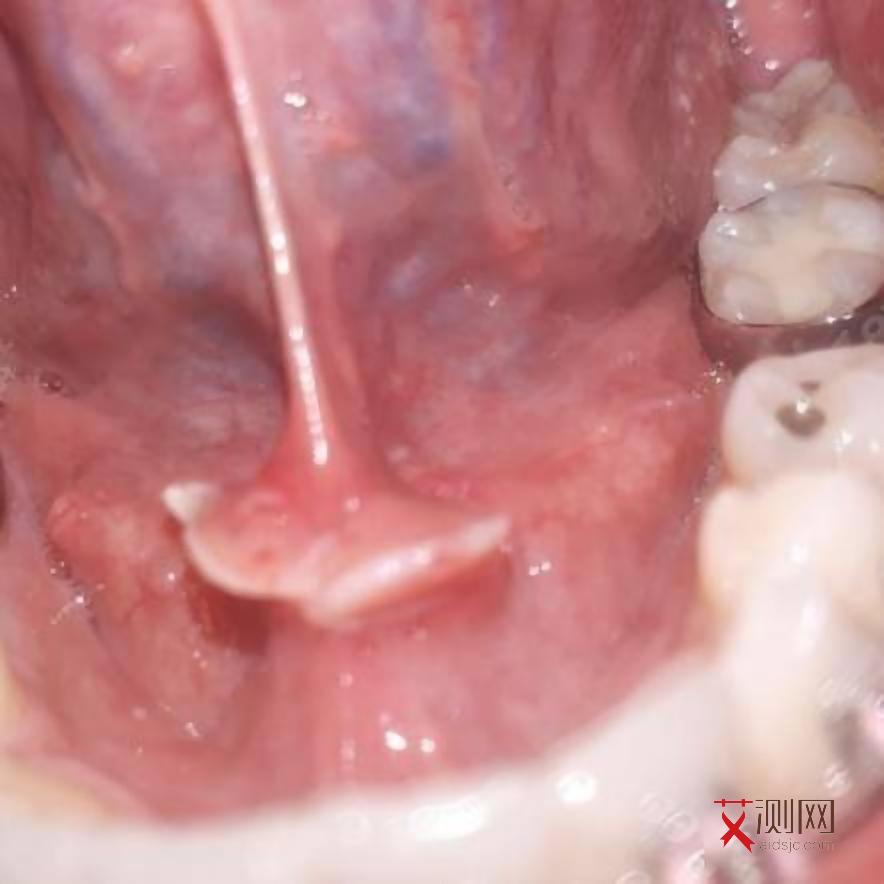

除了皮疹,部分患者还可能出现口腔黏膜的病变,如口腔溃疡。口腔溃疡的面积可能较大,边缘不规则,疼痛较为明显,严重影响患者的进食和说话。而且,这种口腔溃疡往往反复发作,难以愈合。